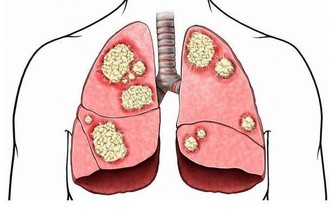

顱內壓增高

無論是顱腦外傷、炎症或腫瘤,只要引起顱內壓力增高,就會影響眼靜脈的回流,出現視乳頭水腫,損害視神經,嚴重者可導致失明。顱內腫瘤還會直接壓迫視神經或損壞視中樞而造成視野缺損或導致不同程度的非眼病性致盲。所以,一定要加強預防顱腦外傷,重視對腦部炎症和腫瘤的防治。